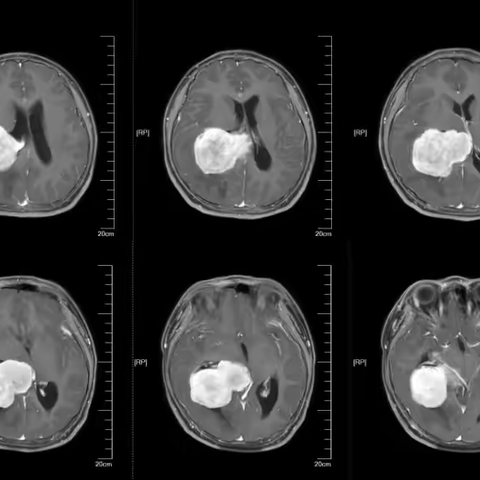

病例分享-侧脑室肿瘤专题

一例巨大侧脑室脑膜瘤